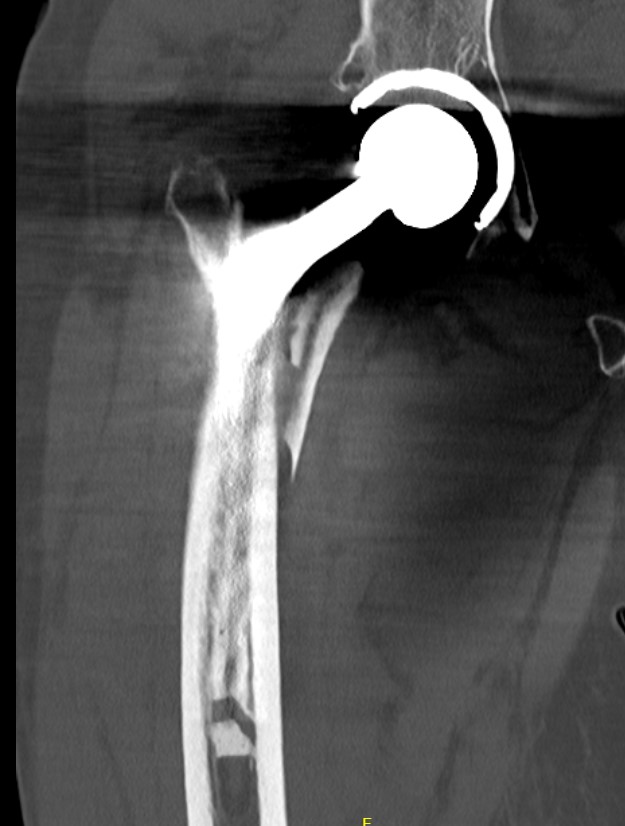

Fracture with stem subsidence around a polished tapered femoral stem treated with ORIF